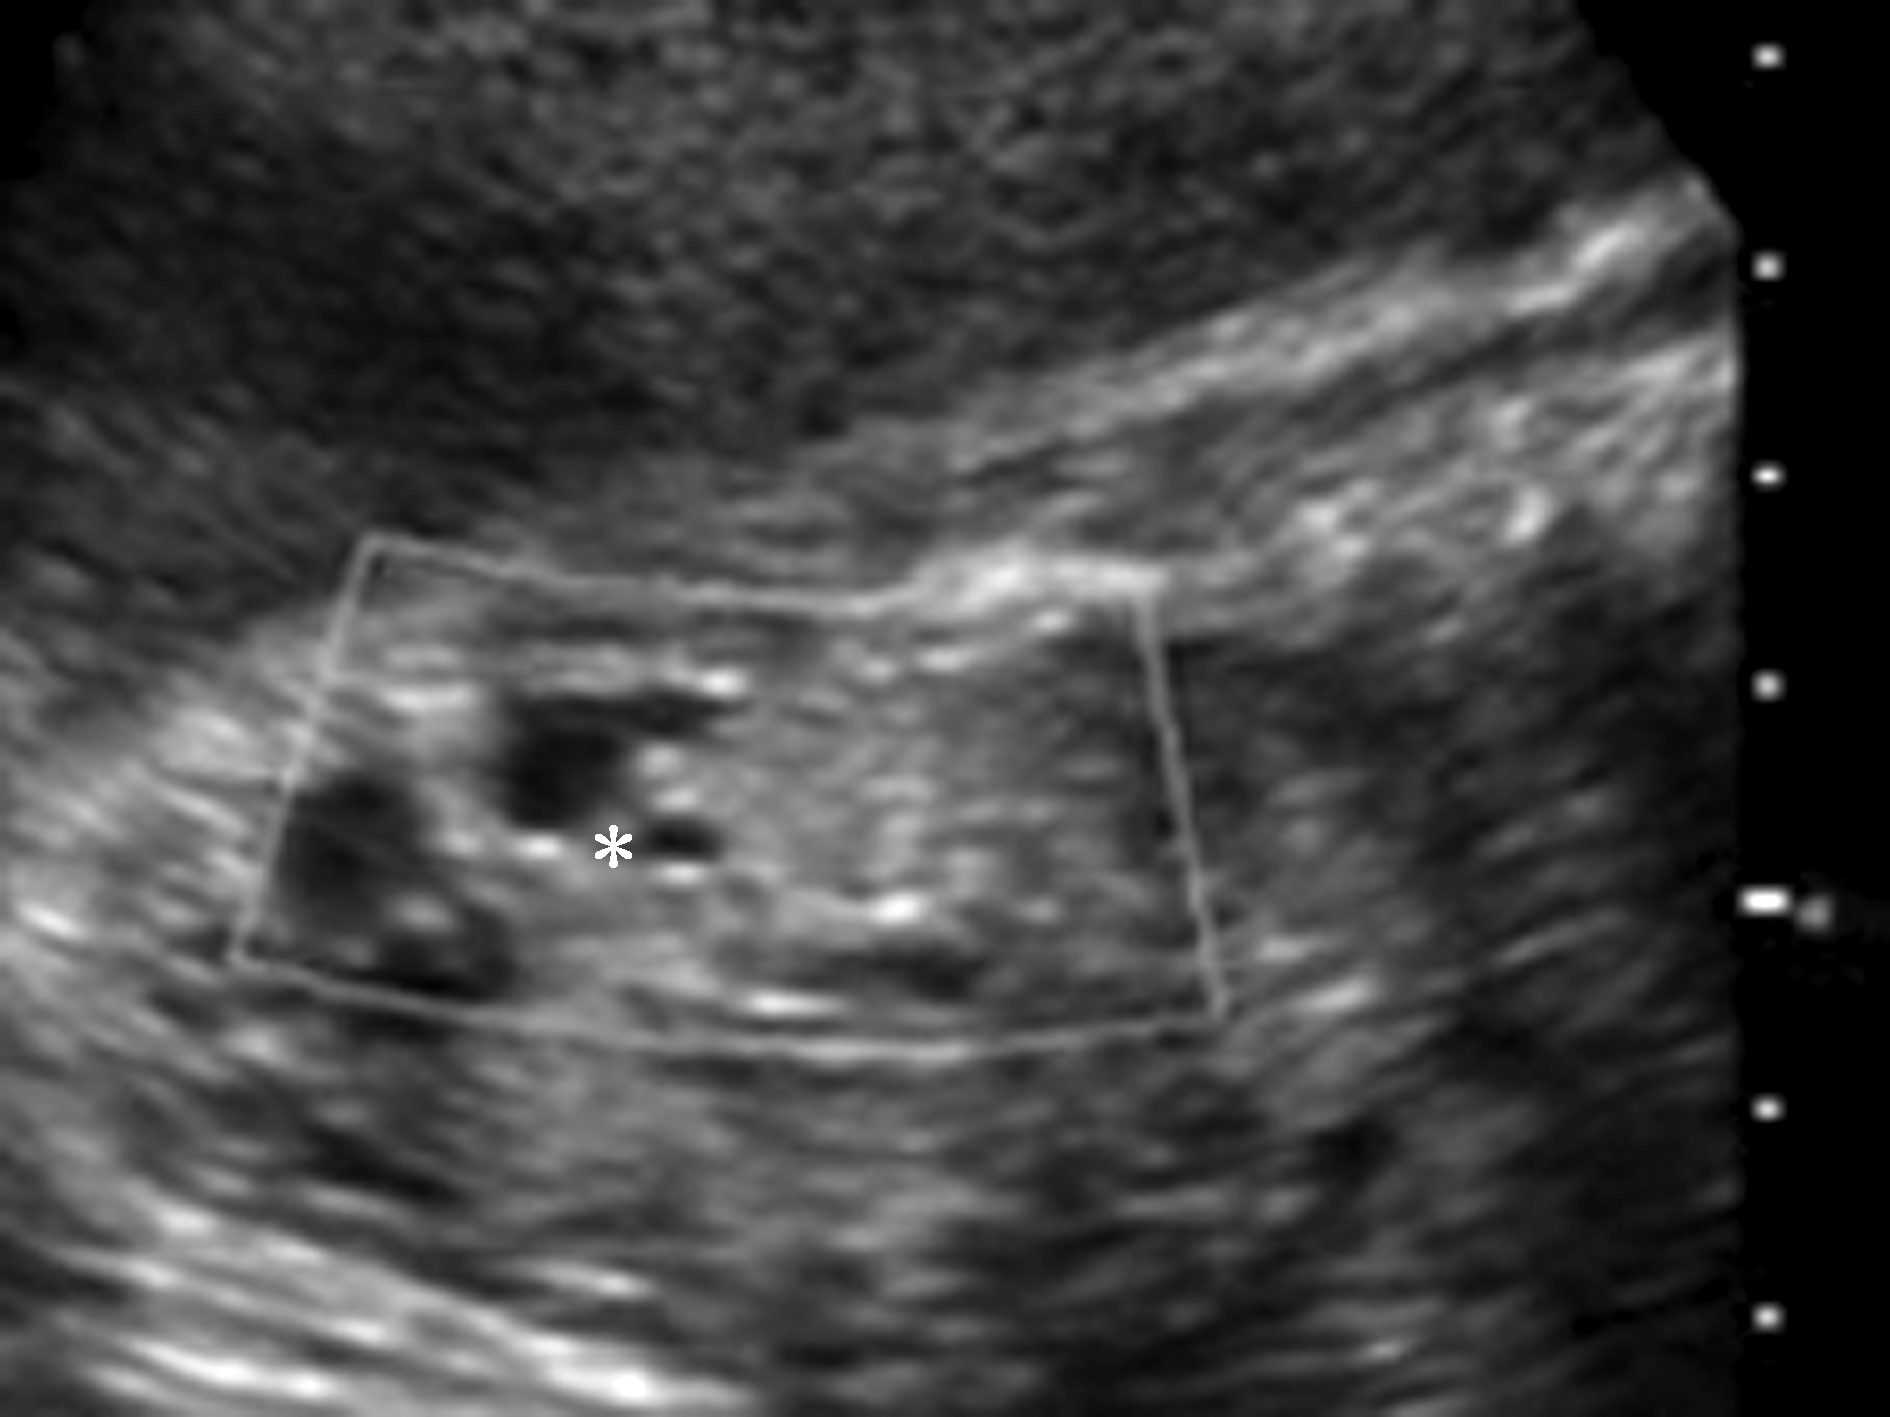

图1胎儿婴儿型多囊肾(A)及成人型多囊肾(B)

本病超声表现与ARPKD相似,亦表现肾脏增大,回声增强,以及肾皮质改变程度与囊的大小程度很不一致(图1B)。但与ARPKD相反的是,ADPKD可较好地显示肾髓质,且肾髓质无明显增大。由于ADPKD不引起胎儿肾功能不全,因此,羊水量在正常范围。

ARPKD产前超声的主要表现有:双侧肾脏对称性、均匀性增大:双侧肾脏回声增强:肾脏回声增强主要在肾髓质部分,而周围皮质部分则表现为低回声(图1A);羊水过少。有研究发现孕12~16周时就可以发现肾脏回声增强,但肾脏形态大小正常。但很多病例在20周前并无异常发现。故有学者提出,孕24周前发现肾肿大并出现肾脏回声增强,即可作ARPKD的诊断。但也应警惕少数胎儿期肾脏回声增强原因可能为正常性的肾脏变异,可能为肾脏皮质和髓质分化增强引起,没有不良临床结局。